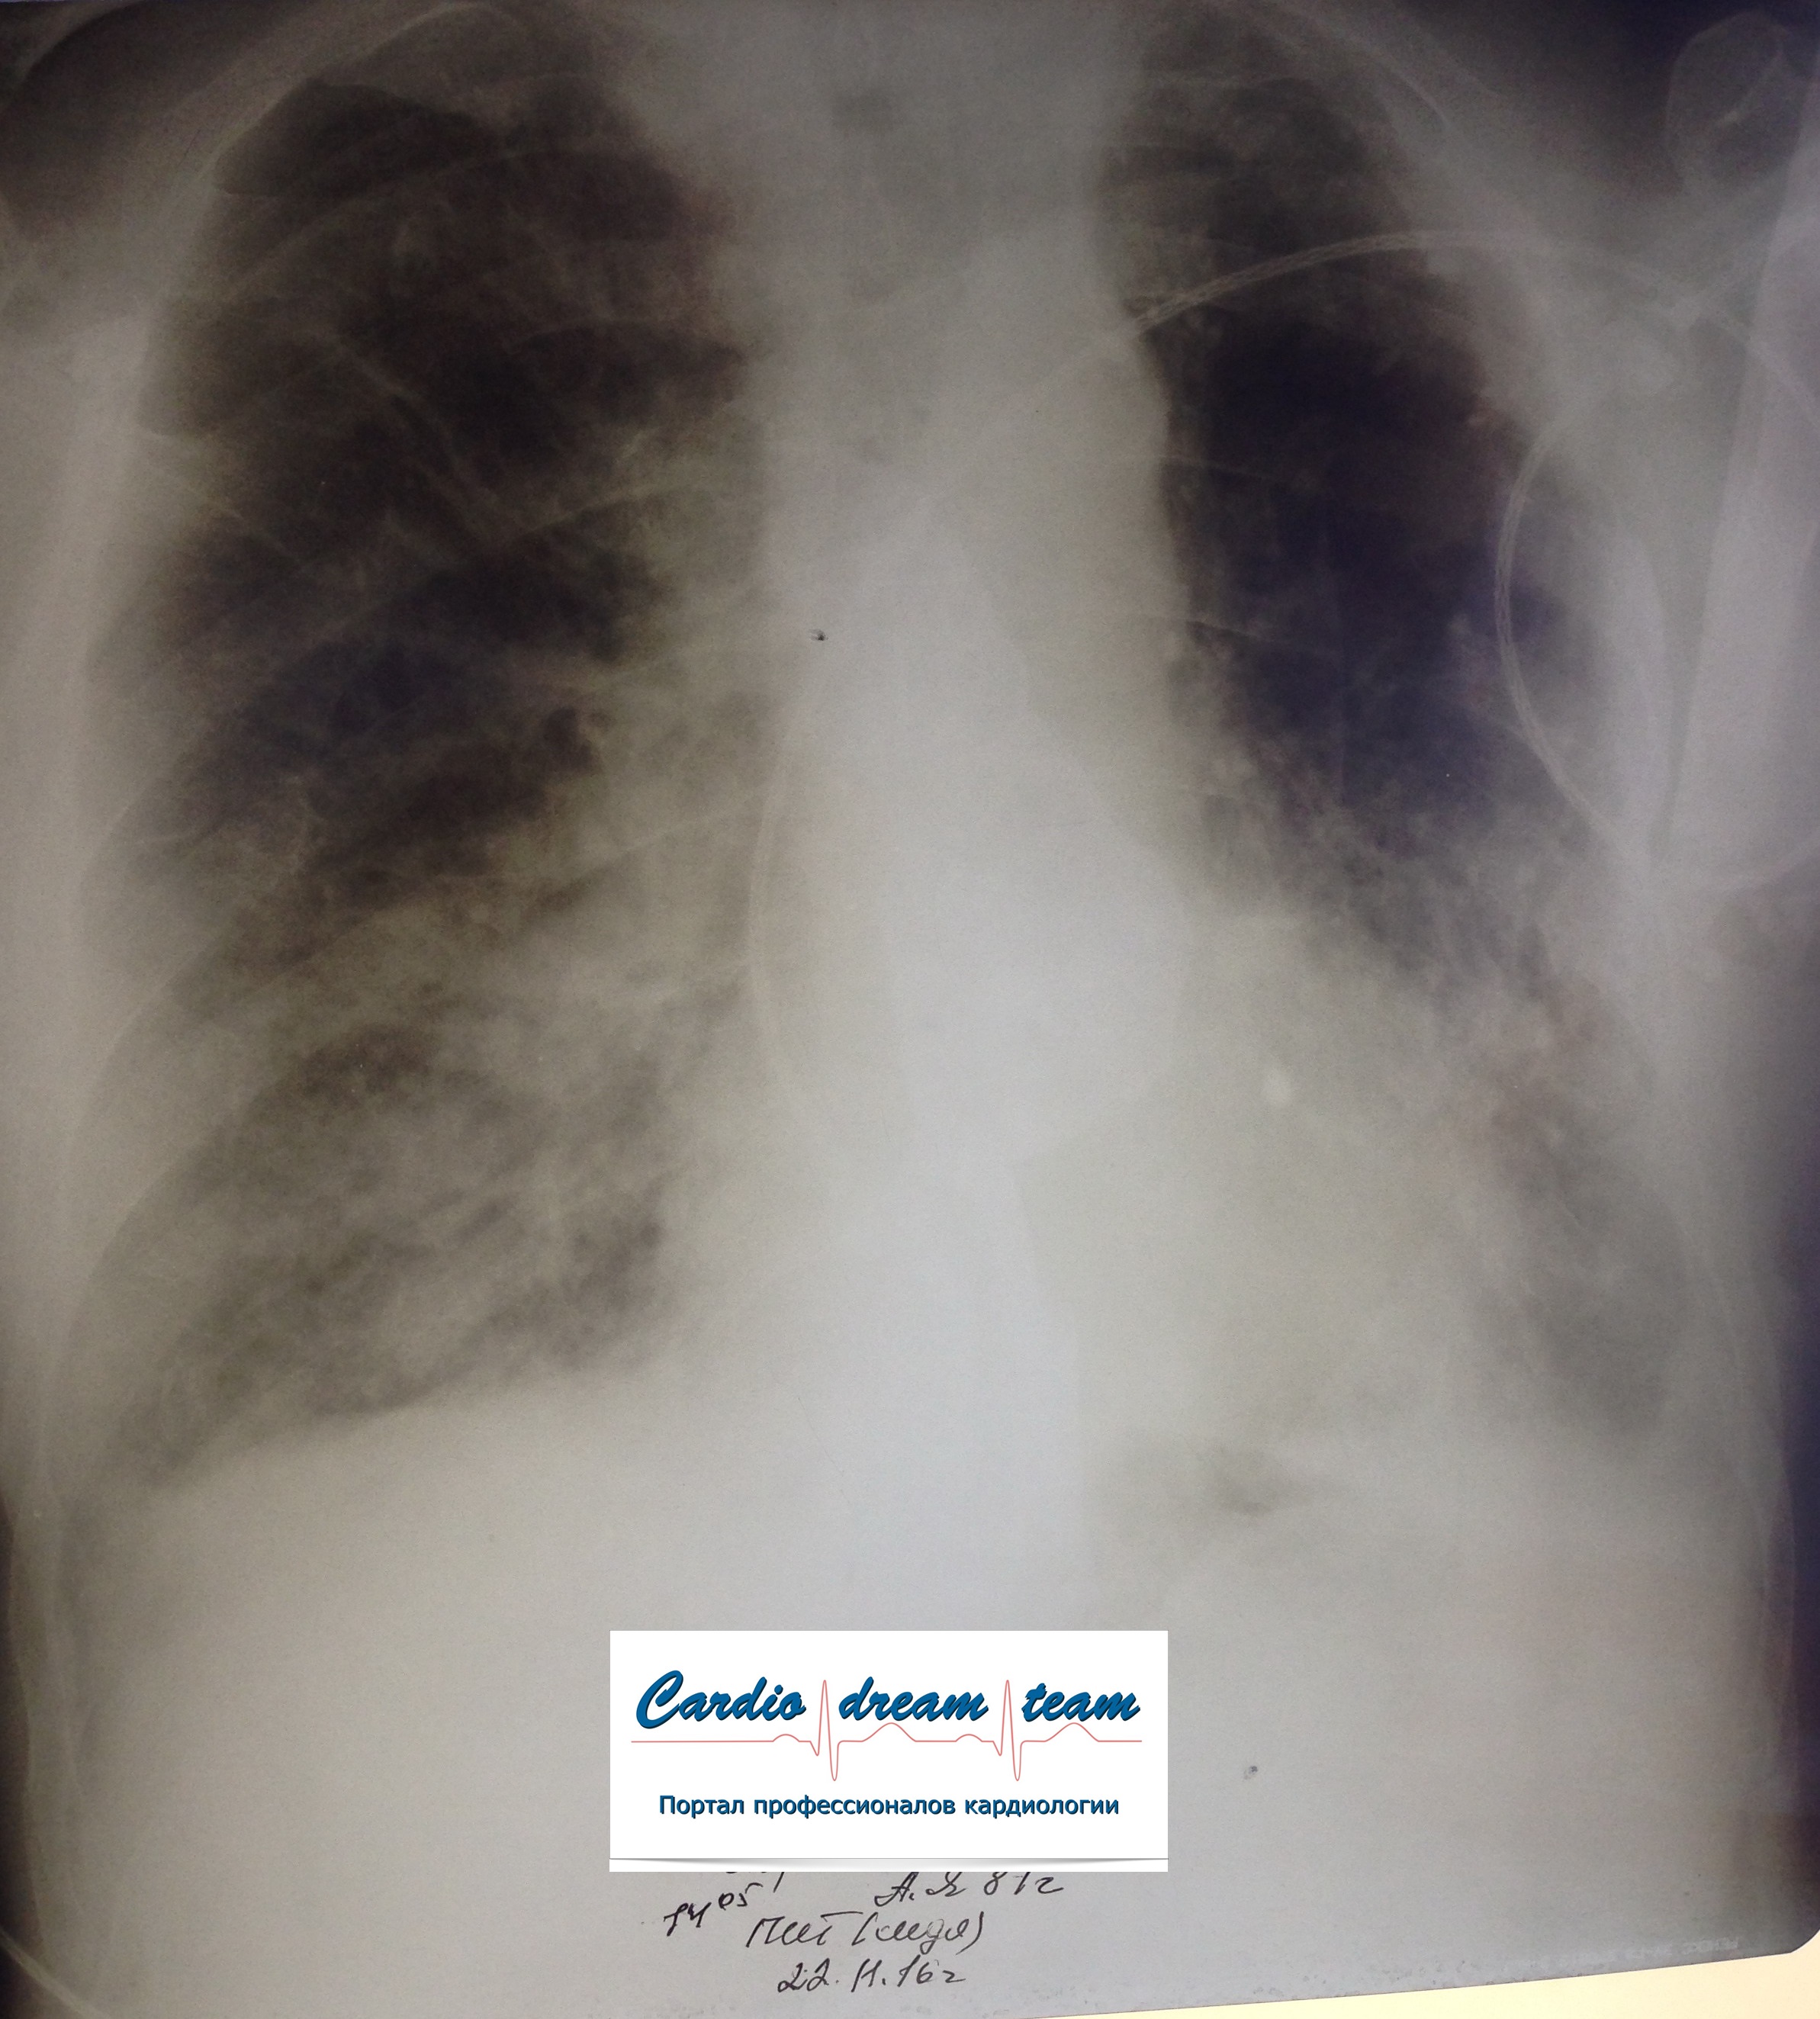

Не обсуждалась Дата 23-ИЮЛ-15 ОПИСАНИЕ: Проведена рентгенография органов грудной клетки в прямой проекции, положение лежа, условия ПИТ Легочные поля: неравномерно прозрачны за счет сосудистого обогащения, в базальных отделах с обеих сторон, отмечается сгущение легочного рисунка, за счет гиповентиляции, в плевральных полостях жидкость Легочный рисунок: Изменен по смешанному типу: обогащен за счет сосудистого компонента, деформирован за счет склероза. Корни: бесструктурны, расширены за счет сосудистого компонента, обогащены Синусы: определяется наличие жидкости по линии 5 ребра Сердце: широко лежит на диафрагме отмечается расширение границ сердечной тени влево, вправо экг-электроды. ЗАКЛЮЧЕНИЕ: Рентген-признаки 2-х стороннего гидроторакса с гиповентиляцией базальных сегментов.. Признаки застоя по МКК 2 степени (умеренно выраженный). Пневмосклероз. Р-признаки гипертрофии левого желудочка сердца. Склероз аорты.